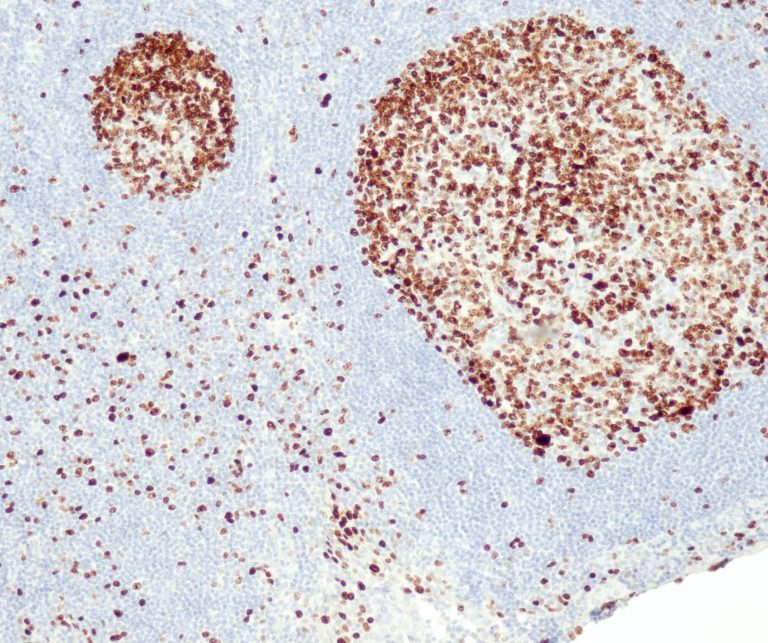

Vascular Pathology

Gastrointestinal (GI) Pathology

General Marker

Breast Pathology

Endocrine Pathology

Gynecological Pathology

Neuropathology

Infection Markers

Lung Pathology

Urinary Tract Pathology

Transplantation Pathology

Soft Tissue Pathology

Hematopathology